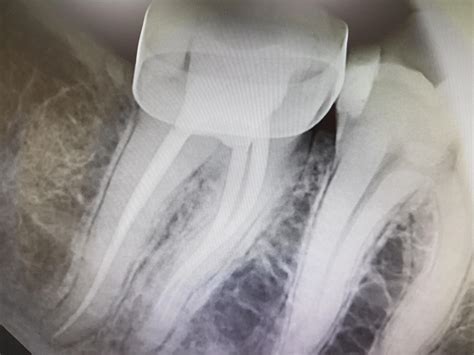

How to Take PERFECT Dental X-rays

How to Take PERFECT Dental X-rays